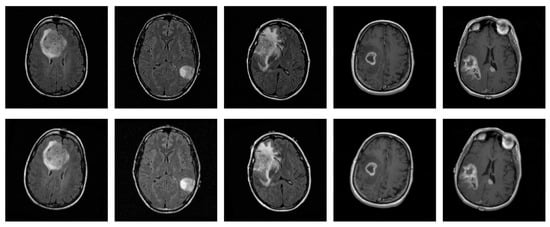

Deep learning models for three-dimensional (3D) data are increasingly used in domains such as medical imaging, object recognition, and robotics. At the same time, the use of AI in these domains is increasing, while, due to their black-box nature, the need for explainability has grown significantly. However, the lack of standardized and quantitative benchmarks for explainable artificial intelligence (XAI) in 3D data limits the reliable comparison of explanation quality. In this paper, we present a unified benchmarking framework to evaluate both intrinsic and post hoc XAI methods across three representative 3D datasets: volumetric CT scans (MosMed), voxelized CAD models (ModelNet40), and real-world point clouds (ScanObjectNN). The evaluated methods include Grad-CAM, Integrated Gradients, Saliency, Occlusion, and the intrinsic ResAttNet-3D model. We quantitatively assess explanations using the Correctness (AOPC), Completeness (AUPC), and Compactness metrics, consistently applied across all datasets. Our results show that explanation quality significantly varies across methods and domains, demonstrating that Grad-CAM and intrinsic attention performed best on medical CT scans, while gradient-based methods excelled on voxelized and point-based data. Statistical tests (Kruskal–Wallis and Mann–Whitney U) confirmed significant performance differences between methods. No single approach achieved superior results across all domains, highlighting the importance of multi-metric evaluation. This work provides a reproducible framework for standardized assessment of 3D explainability and comparative insights to guide future XAI method selection.